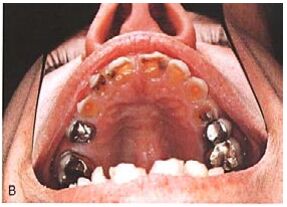

29. 男性 55 歲卡車司機,有 ABC 病史均超過十年以上,上次就診紀錄是五年前,因牙痛求診治療,經口腔專業諮詢師進行口內檢查後發現口內嚴重齲齒,中度牙周炎情形,且在患者上顎黏膜組織中出現異常病灶,請問上顎黏膜組織病灶為何?(A) Abscess (B) Beneath a denture (C) Circumvallate Papillae (D) Nicotinic stomatitis